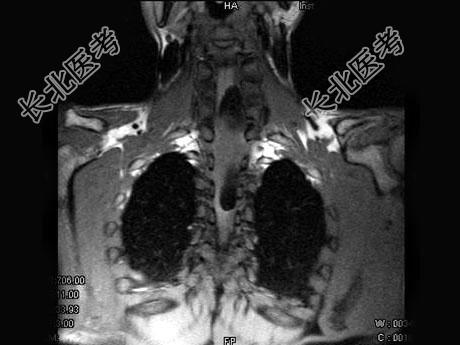

单项选择题男,37岁, 肢体活动不利、酸胀1年余,MRI扫描见椎管内长条形T1和T2高信号, 脂肪抑制序列呈低信号,应考虑为 ( )